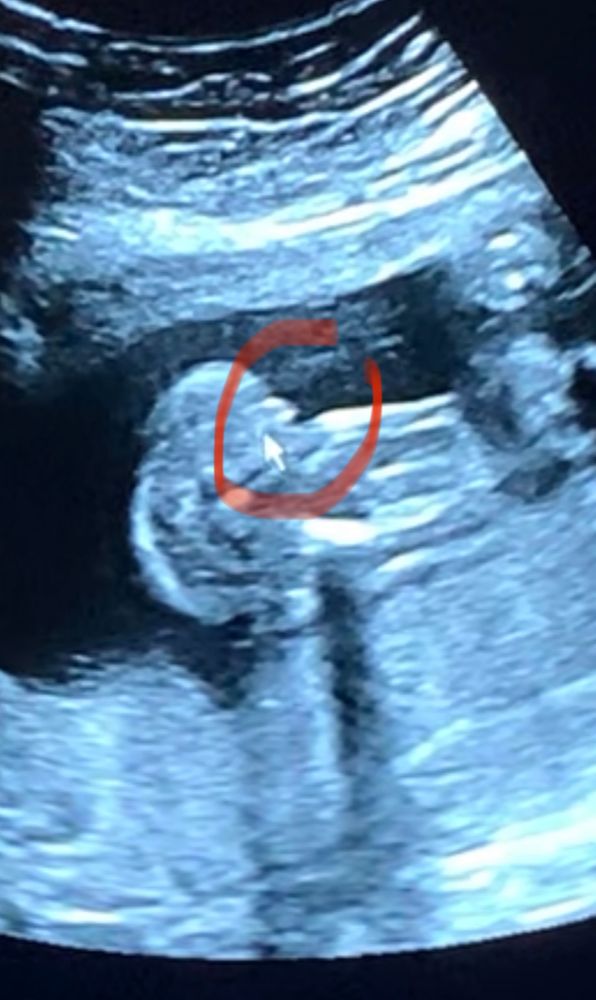

Пол ребёночка ❤️

На всех узи скрещиваем ноги. На прошлой недели (была 21 неделя), не выдержали и пошли на платный скрининг с целью узнать пол. Ноги как всегда оказались скрещённые 😹

Врач сказал, формируются половые губы по узи. Подруге говорили тоже самое, в итоге «половые губы» спустились и стали яичками. У кого было так же ?

На вашем фото не понимаю, что где... Вернее, я поняла область, которую Вы обвели, но там неясно, что это такое, какой ракурс. Не увидела ни мошонку с перчиком, ни кофейное зернышко))